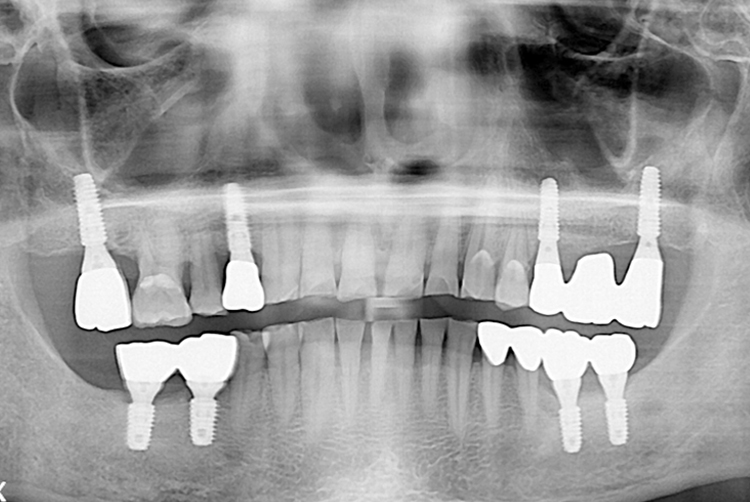

[임플란트] 임플란트

치료전 : 2019-09-11

세종치과는 많은 환자와 다양한 케이스를 바탕으로 항상 편안한 임플란트 수술을 제공하고자 노력하고,

오래동안 튼튼히 쓸 수 있는 임플란트 수술을 가장 큰 목표로 삼고 있습니다